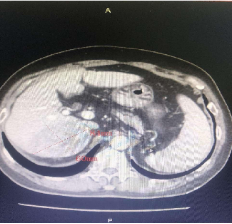

增强ct可见肝右叶占位病变

此次来院检查腹部增强CT提示:肝右叶占位性病变,考虑为原发性巨块肝癌,肿瘤大小达到60mmx84mm。患者之前已进行过结肠癌根治性右半结肠切除+胆囊切除术,病情复杂,身体虚弱,患者及家属强烈要求行微创介入治疗。经术前充分沟通及告知各种治疗方案的优缺点后,介入团队选择为患者行TACE介入微创治疗,后续将与靶向、免疫联合治疗达到肝癌的综合治疗。经过积极术前准备,普外科介入团队成功为患者实施了首例肝动脉化疗栓塞术,手术过程顺利,术后患者恢复良好,正在医院接受后续治疗。